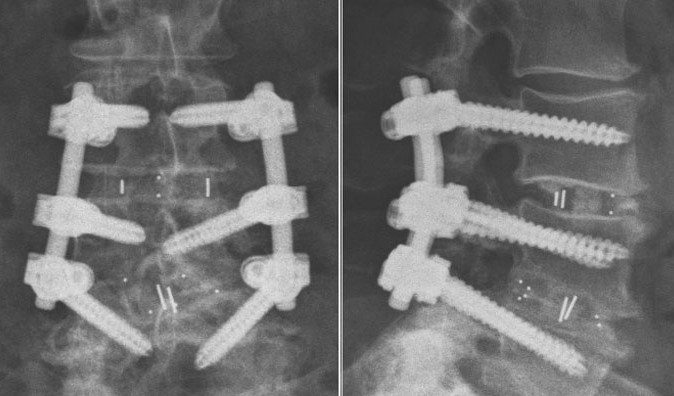

2 сентября в виварии Приволжского медуниверситета выполнены три последовательные операции по имплантации экспериментальных титановых систем для фиксации позвоночника карликовым свиньям.

Титановые имплантаты – совместная разработка врачей и учёных Университетской клиники ПИМУ и малого предприятия «Виптехнологии». Промышленным партнёром выступает Арзамасский приборостроительный завод.